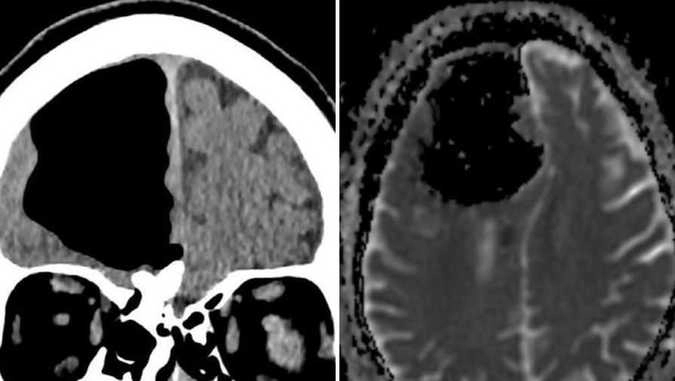

Дальше врачи сделали мужчине компьютерную томографию, которая показала, что на месте правой лобной доли находилась пустота. Опытные специалисты больницы заявили, что ничего подобного прежде не видели.

Осуществленная впоследствии магнитно-резонансная томография показала образовавшуюся в передней части черепа заполненную воздухом полость, которая достигала 9 см в поперечнике. Подобное явление называют «пневматоцеле»: оно может наблюдаться после травм, инфекций или хирургических операций.